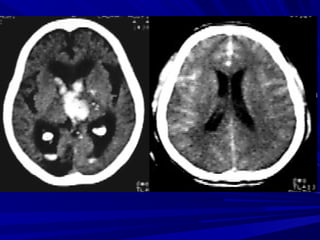

Nhồi máu não cũ

Xuất huyết sau

nhồi máu

Nhồi máu vùng nuôi ĐM não giữaNhồi máu vùng nuôi ĐM não giữa

Nhồi máu vùng nuôi động mạch nãoNhồi máu vùng nuôi động mạch não

sausau